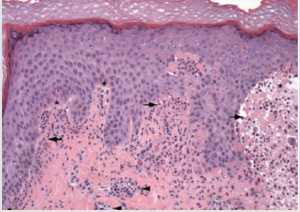

The diagnosis of dermatitis herpetiformis is based on a combination of physical examination, routine histopathological examination, immunofluorescence examination, and serological testing. Physical examination alone can lead to the diagnosis, but due to the varying morphological appearance of dermatitis herpetiformis, additional examinations are often required to assist in the diagnosis. Routine biopsy specimens should be taken from intact vesicles. The typical histopathological appearance of dermatitis herpetiformis when examined under a light microscope is a subepidermal cleft with neutrophils and some eosinophils in the papillary dermis as shown in Figure 2. These findings are often found along with mixed inflammatory infiltrates around the blood vessels [10].

Figure 2: Electron microscope scan in dermatitis herpetiformis. Light microscope shows neutrophiles (black arrow) and subepidermal cleft (star), and inflamation infiltrat in perivaskular (black arrow) [1].